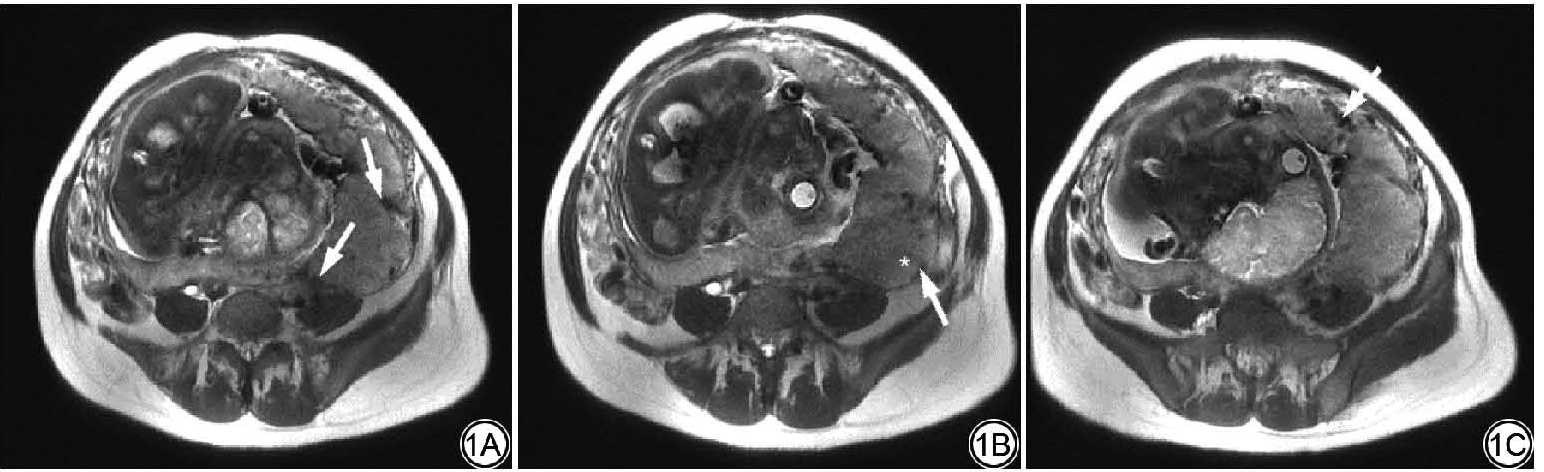

根据新版美国腹部放射学会和欧洲泌尿生殖放射学会发布的联合共识,总结归纳了11个与PAS相关的MRI征象(部分典型MRI征象如图1),包括:(1)胎盘附着处肌层变薄,<1 mm或局部中断;(2)T2WI上胎盘与子宫肌层界面低信号线消失;(3)胎盘床异生血管(包括肌层、肌层-胎盘界面);(4)T2WI上胎盘内条片状低信号带;(5)胎盘内血管异常(粗大血管或较大血窦);(6)胎盘不对称增厚,>5 cm;(7)胎盘凹陷或缺血性梗死;(8)局灶外生性包块;(9)子宫-胎盘局限性膨出;(10)膀胱壁中断,膀胱血管征或“帐篷征”;(11)子宫周围结构受侵。所有入组对象MRI征象的评估分别由2名妇产放射医师(分别为临床诊断经验超过5年和10年的主治医师及副主任医师)在PACS系统中独立完成,当2名医师的诊断结果出现分歧时,上级医师(1名临床诊断经验超过20年的主任医师)诊断作为最终结果。为减少偏倚,参与评估征象的放射医师对患者的手术结果和临床资料保持盲法。

图1  女,32 岁,病理诊断为胎盘植入。T2WI 显示与PAS 相关的征象,胎盘内低信号带(1A;箭),子宫肌层变薄或中断(1B;箭)及子宫-胎盘局限性膨出(1B;星形),胎盘床异生血管(1C;箭)。PAS:胎盘植入性疾病。

Fig. 1  A 32-year-old female patients pathologically diagnosed with placenta increta. T2WI features associated with PAS intraplacental T2 dark bands (1A; arrow), myometrial thinning or disruption (1B; arrow) and uterine-placental bulge (1B; star), abnormal vasculature of the placental bed (1C; arrow). PAS: placenta accreta spectrum.